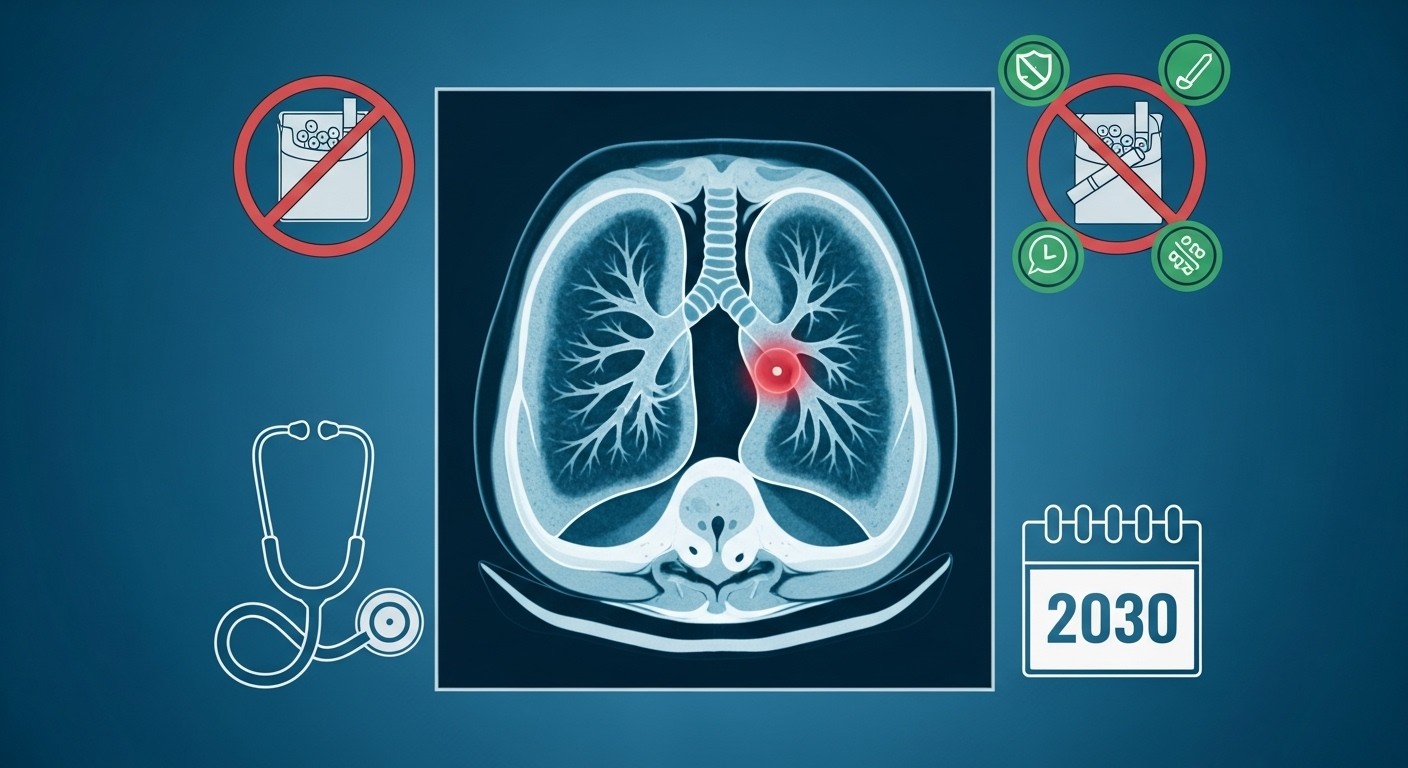

Et si on pouvait vraiment changer la donne face au cancer le plus meurtrier en France ? Chaque année, plus de 30 000 personnes perdent la vie à cause du cancer du poumon. C’est énorme, presque insupportable quand on sait que la majorité des cas sont découverts trop tard. Mais voilà, les choses bougent enfin sérieusement. Les autorités sanitaires préparent un dépistage organisé, comme on en a déjà pour le sein ou le côlon, et l’objectif affiché est ambitieux : le généraliser d’ici 2030. Personnellement, je trouve ça presque révolutionnaire, parce que pour une fois, on ne se contente pas de soigner, on cherche à prévenir vraiment les drames.

Le cancer du poumon reste en tête des causes de décès par cancer dans l’Hexagone. Pourtant, contrairement à d’autres tumeurs, il n’avait pas encore bénéficié d’un vrai programme de dépistage populationnel. Ça change. Les annonces récentes marquent un tournant : un projet pilote ambitieux démarre très prochainement, avec des milliers de volontaires qui vont passer des scanners réguliers. L’idée ? Repérer les lésions précoces, quand les chances de guérison explosent littéralement.

Pourquoi maintenant ? Parce que les études internationales ont prouvé depuis longtemps que le dépistage par scanner faible dose chez les gros fumeurs ou ex-gros fumeurs réduit significativement la mortalité. On parle de 20 % en moyenne, et parfois plus chez les femmes. C’est énorme. Et pourtant, la France traînait des pieds. Aujourd’hui, on accélère.

Le cœur du dispositif, c’est le scanner thoracique à faible dose, voire ultra-faible dose. L’examen est rapide, indolore, et expose à une irradiation très limitée – bien moins qu’un scanner classique. Les participants feront deux scanners à un an d’intervalle, puis un tous les deux ans si tout va bien.

Aujourd’hui, trois quarts des cancers du poumon sont diagnostiqués à un stade avancé. Résultat : moins d’un patient sur quatre est encore en vie cinq ans après. Avec un dépistage précoce, on inverse la tendance : jusqu’à trois quarts des diagnostics pourraient se faire à un stade opérable, avec des traitements beaucoup moins lourds – chirurgie mini-invasive, radiothérapie ciblée, etc. Les chances de guérison grimpent en flèche.